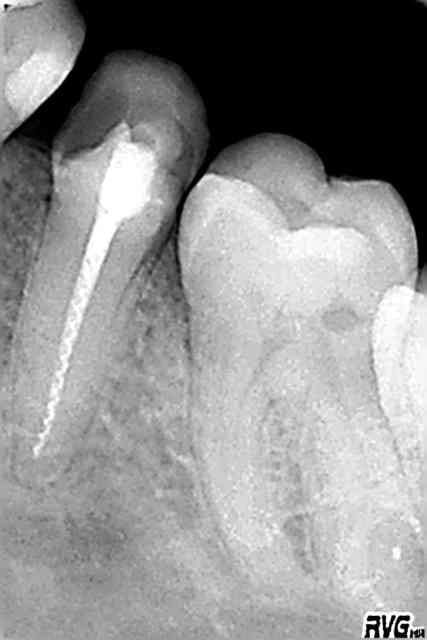

radios

R1 uq8spw - Eugenol

R2 hscwt1 - Eugenol

R3 bceowk - Eugenol

R4 vrw98y - Eugenol